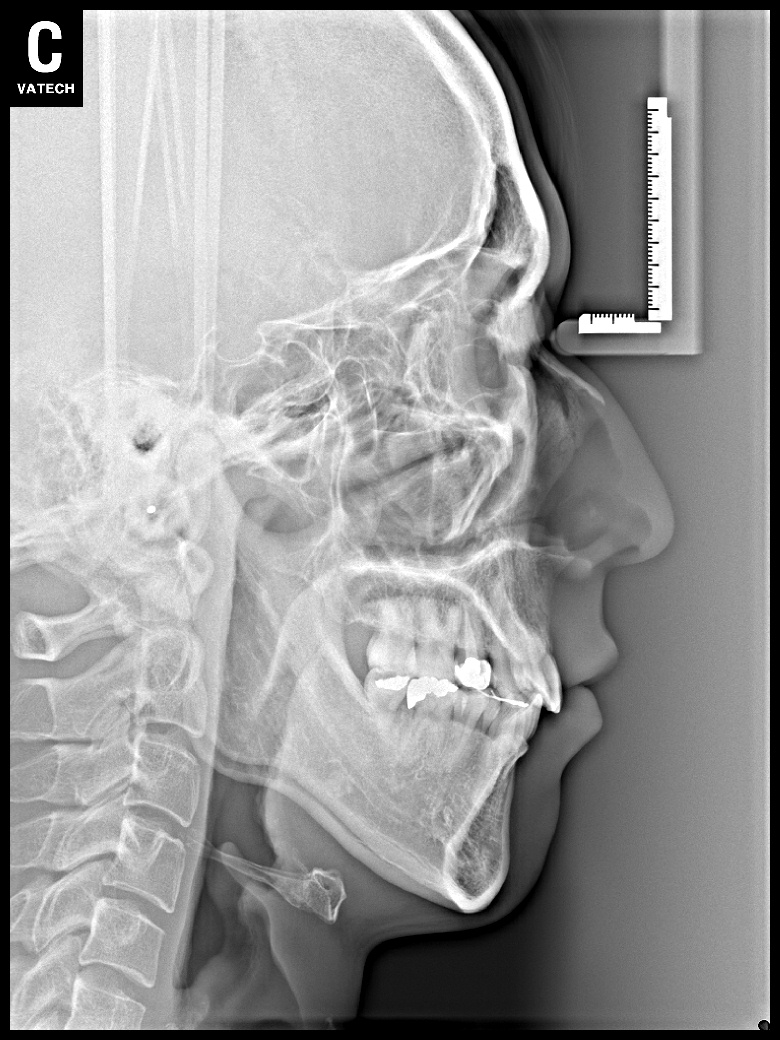

치료 전 사진입니다.